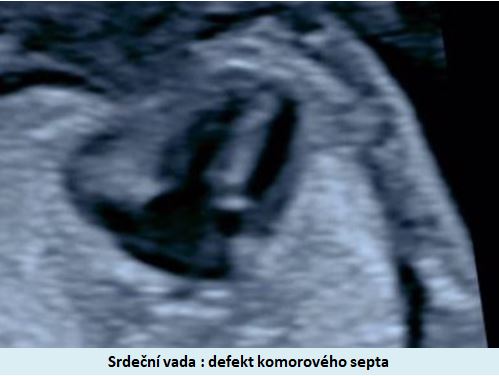

patří mezi nejznámější syndromy způsobené chromozomální aberací. V klasické formě je způsoben trizomií chromozomu 21. Je nejčastější vrozenou příčinou mentální retardace. Charakteristickými znaky jsou typický vzhled a srdeční vady .

Ultrazvuková diagnostika se při screeningu v 1. trimestru opírá o šířku podkoží v záhlaví plodu, osifikaci nosní kůstky a nálezu abnormálních průtoků v srdci plodu (trikuspidální regurgitace, reversní tok v ductus venosus).

Pracoviště se zkušenostmi v prenatální diagnostice a s dobrým přístrojovým vybavením je schopno vyslovit podezření na tento syndrom ve více jak 90% případů již při ultrazvukovém vyšetření ve 12-13. týdnu těhotenství. .